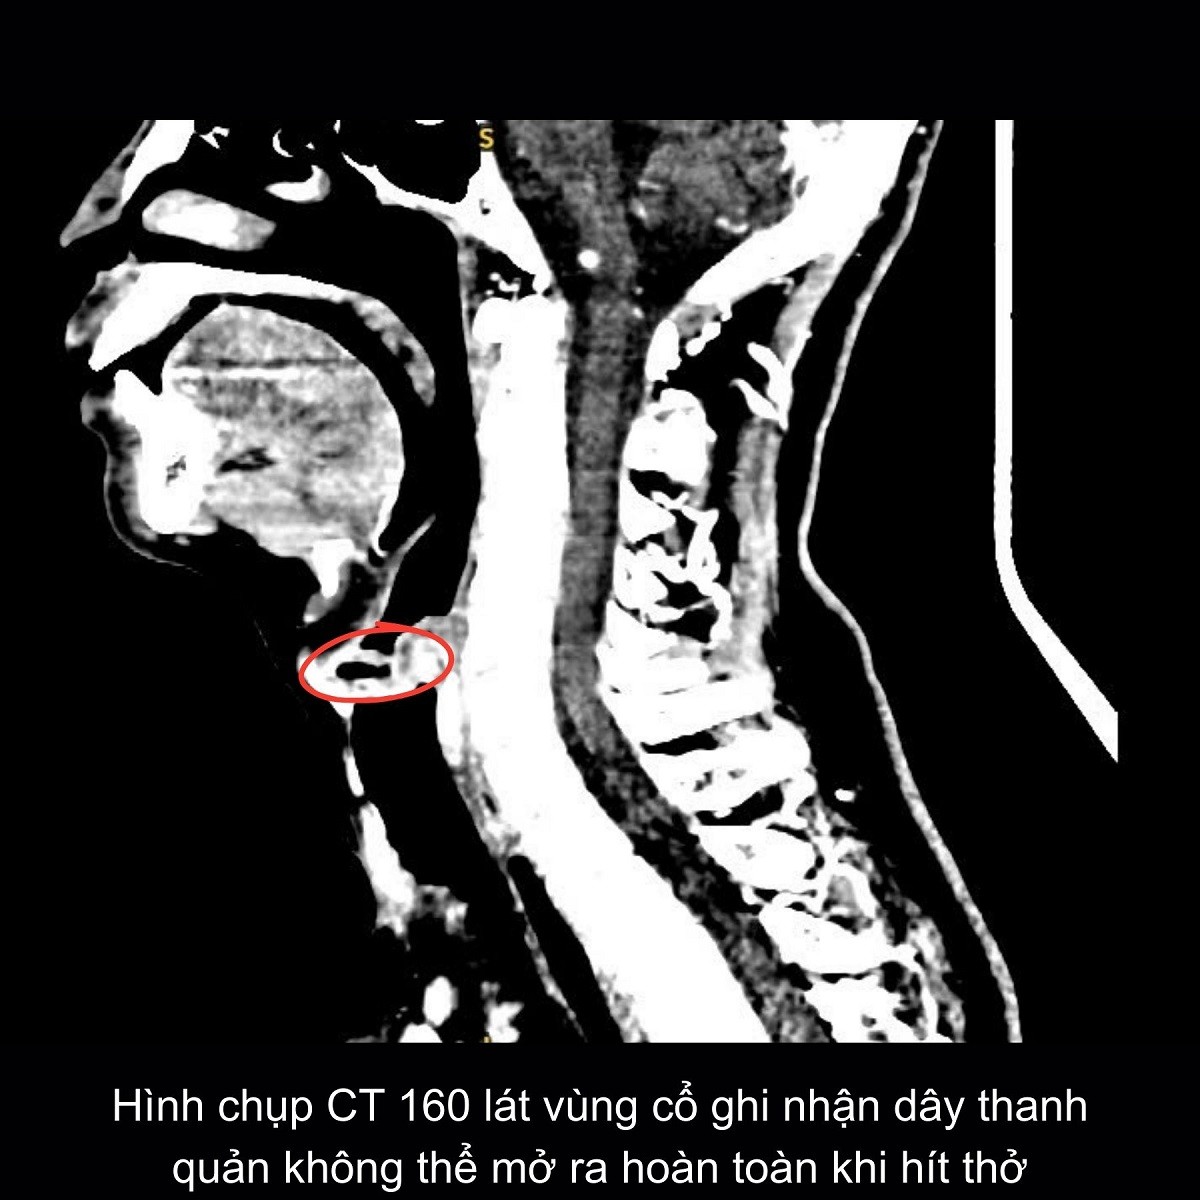

Tại đây, các bác sĩ chuyên khoa Tai Mũi Họng tiến hành soi họng, chụp MRI sọ não và CT vùng cổ – ngực. Kết quả cho thấy bệnh nhân bị liệt khép dây thanh 2 bên, khiến dây thanh không thể mở ra khi hít thở. Đây là tình trạng hiếm gặp nhưng đặc biệt nguy hiểm, có thể dẫn đến khó thở cấp và suy hô hấp nếu không can thiệp kịp thời.

Trước nguy cơ bệnh tiến triển nặng, các bác sĩ quyết định phẫu thuật cắt bán phần dây thanh phải nhằm mở rộng đường thở, đảm bảo hô hấp cho người bệnh.